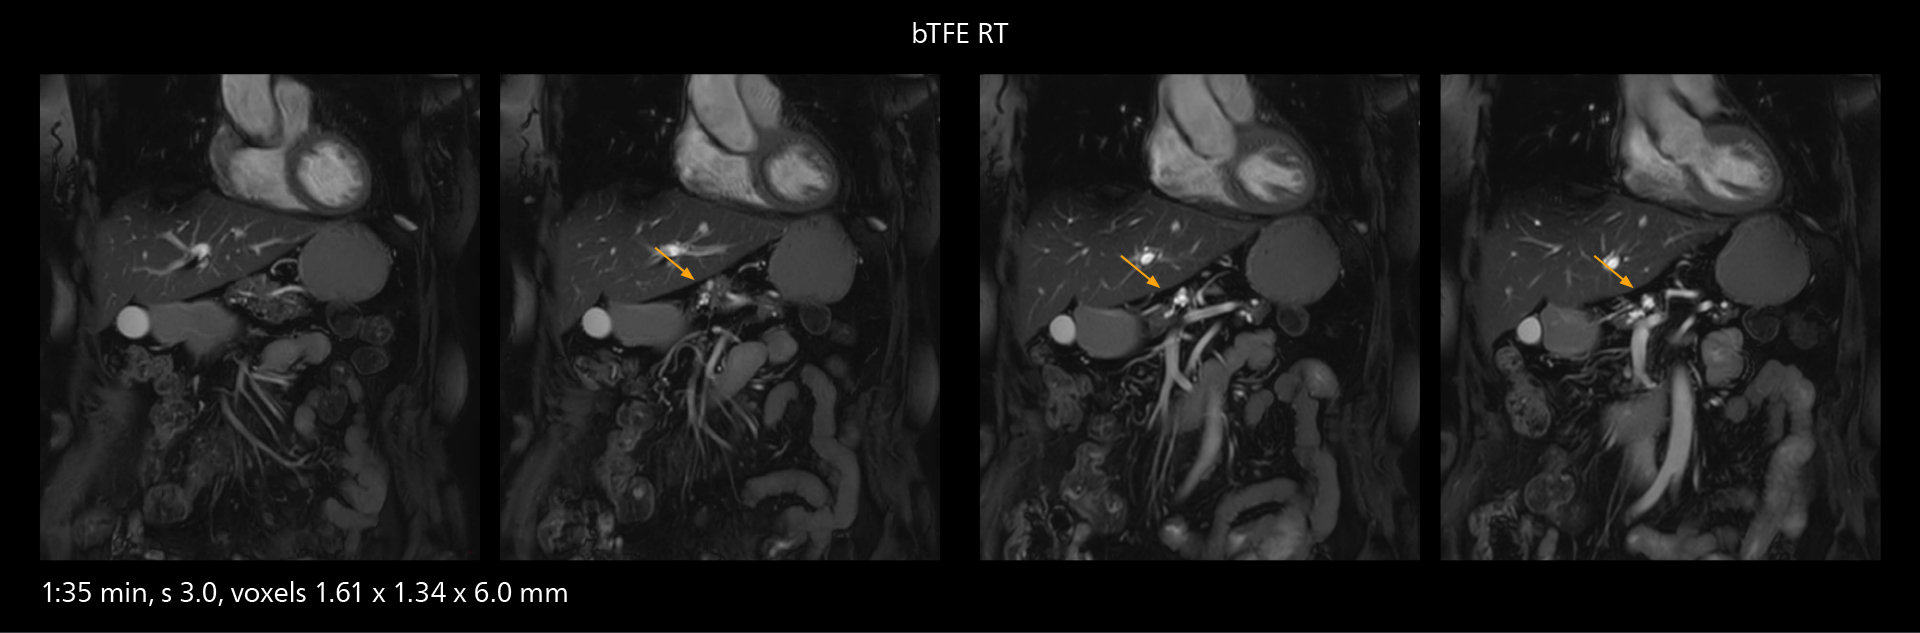

MRI of prostate

Examples of prostate imaging showing faster scan times and improved resolution illustrate the power of SmartPath to Elition X in this case of prostate cancer with PI-RADS score 4.